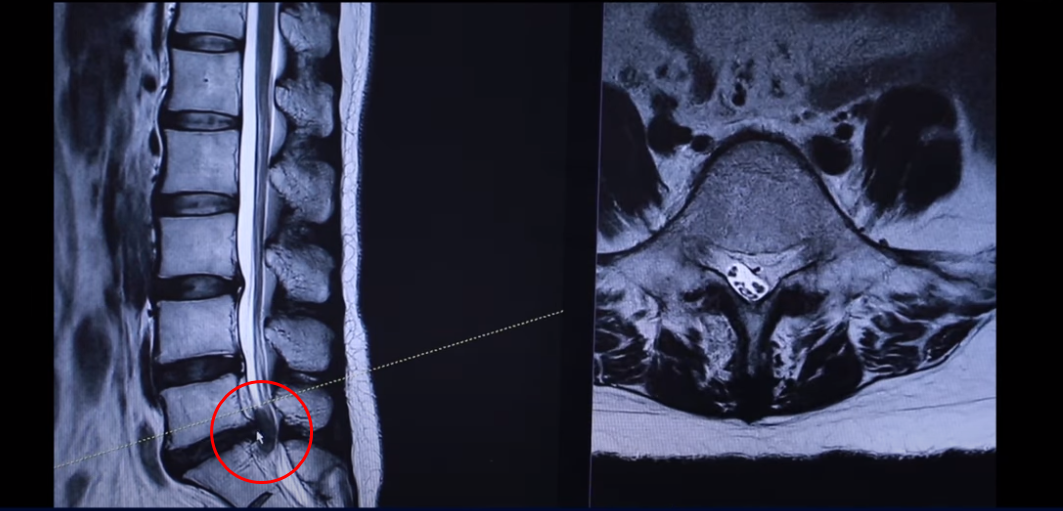

43세 여자 허리 디스크 파열 환자분 MRI 보도록 하겠습니다. 이분은 파열이 어마어마하게 심합니다. 세 마디에 퇴행성 디스크가 있는데 5번 1번을 보면 위와 아래로 밀려 올라가 있죠.

터져서 밀려나온 디스크 수핵이 위와 아래로 밀려 나가 있습니다. 보시면 이쪽이 왼쪽입니다. 환자의 왼쪽을 완전히 덮어버렸죠.

그래서 역시 이분 증상은 왼쪽 다리 방사통입니다. 왼쪽 다리 방사통과 왼쪽 다리 마비 증상 운동 마비는 심하지 않고 감각 마비가 심합니다. 발가락 발바닥 이런 데 감각을 느끼지 못하는 감각 마비 증상이 있습니다. 사실은 이 정도면 운동 마비도 있을 만한데 예를 들면 까치발이 안 된다든가 아니면 족하수 증상이 있다든가. 그런데 그런 운동마비 증상은 없으셨습니다. 너무너무 많이 터졌기 때문에 수술 병원에 가서 즉시 전신 마취를 해서 수술을 해야 된다고 듣습니다.

다시 동생분 MRI로 돌아가겠습니다. 언니분하고 똑같이 이 동생분 세 마디 디스크가 퇴행돼 있죠 그리고 마지막 마디가 터져서 이렇게 왼쪽으로 심하게 밀려 나가 있습니다.

언니분보다 터진 정도는 더 심합니다. 그래서 이렇게 디스크가 심하게 파열되고 또 마비 증상까지 있는 분들 이런 분들은 이 환자분이 들으신 것처럼 정형외과나 신경외과에서 즉시 수술을 해야 된다. 또 마비 증상까지 있으니까 바로 수술을 하지 않으면 마비 증상이 오래되면 신경이 심하게 눌려 있으면 신경 기능이 많이 떨어지면 만약 마비가 풀리지 않는다고 그러면 그건 이제 장애가 되는 거죠. 그렇기 때문에 즉시 수술을 해야 된다 이렇게 듣는데 이렇게 파열이 심한 분들일수록 저희는 오히려 비수술 재활 치료가 성공할 확률이 더 높다. 역설적이게도 파열이 심하면 심할수록 치료가 더 잘될 확률이 높다. 저희 모커리한방병원이 이렇게 설명을 하고 있는데 왜 그럴까요?